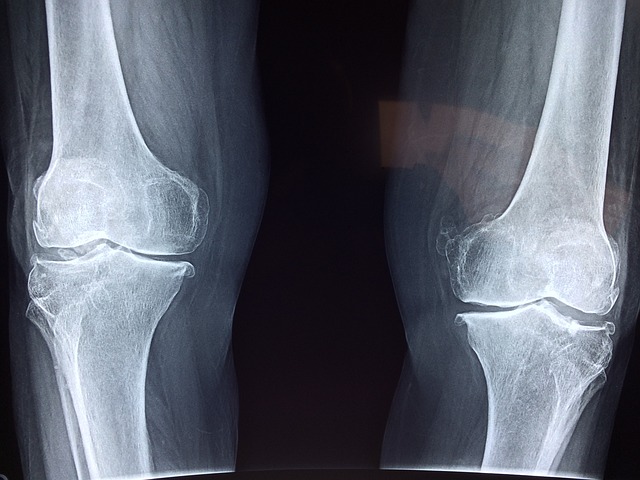

7. 무릎

무릎이 아픈 분들은 무릎 통풍도 의심해 볼 수 있습니다. 통풍은 무릎에서 발생하는 경우도 많은데요. 무릎 통풍 증상이 나타나면 무릎을 굽혔다 펴기가 힘들 정도로 통증이 발생하고 무릎 부위가 부어오르는 증상이 나타납니다.